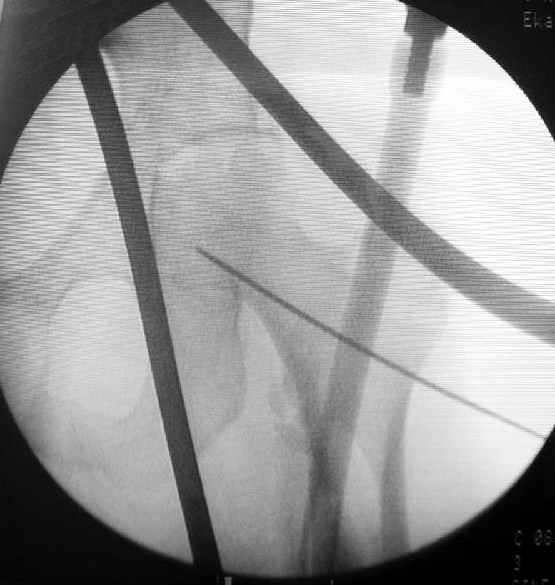

Как раз недавно у меня был примерный случай: больному 36 лет, поступил ночью, травма в результате мотоциклетной аварии, кроме чрезвертельного и спирального перелома левого бедра имеется переломы костей предплечья с этой же стороны. Скелетное вытяжение, а на следующий день больной про оперирован на ортопедическом столе с дистракцией. Чтобы не расколоть чрезвертельный перелом провели временную спицу ближе к переднему кортексу, из малого разреза костодержатель для репозиции, а фиксацию провели антиградным штифтом. Этапы операции на снимках.

DK> Чтобы не расколоть чрезвертельный перелом провели временную спицу

DK> ближе к переднему кортексу,